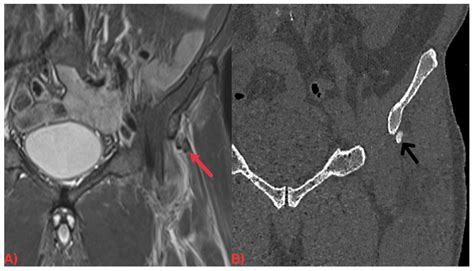

HADD can affect various joints, including the shoulder, elbow, wrist, hip, knee, and ankle. It can also occur in soft tissues such as tendons and ligaments. The most commonly affected areas are the shoulder and the wrist.

Diagnosing HADD involves a combination of clinical evaluation, imaging studies, and laboratory tests. The diagnostic process typically includes the following steps:

• Imaging Studies: X-rays, ultrasound, and magnetic resonance imaging (MRI) can help identify the presence of hydroxyapatite crystals and assess the extent of the deposits.

Imaging studies are particularly important in diagnosing HADD. X-rays can show calcifications in the affected areas, while ultrasound and MRI provide more detailed images of the soft tissues and joints. Laboratory tests can help rule out other conditions that may cause similar symptoms.